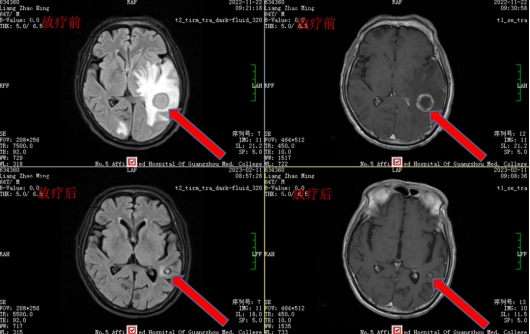

放疗技术出击,精准解决“脑肿”

这时候,梁叔脑水肿症状加重,开始出现幻觉、视力下降、大小便失禁等情况,如果肿瘤进一步增大压迫到脑干组织,随时有呼吸循环障碍、心跳骤停等风险。时间就是生命,石主任团队立即进行多学科讨论制定诊疗计划,认为梁叔目前寡脑转移,可以通过“神奇的光子刀”—放疗来“切除”,达到安全、无痛、高效、低毒的效果,配合全身性治疗。放疗科紧锣密鼓地展开工作,2022年11月开始为梁叔进行脑转移灶放疗,并在放疗期间进行脱水降颅压、镇痛等对症治疗;在放疗几次后,梁叔的症状开始较前明显好转,恢复到从前的生活状态,梁叔也高兴地感叹道:“真的是大难不死,必有后福啊!”。在放疗结束后1月后,梁叔回院复查头颅增强MR,对比治疗前,脑肿竟已完全消失,梁叔终于重获新生。